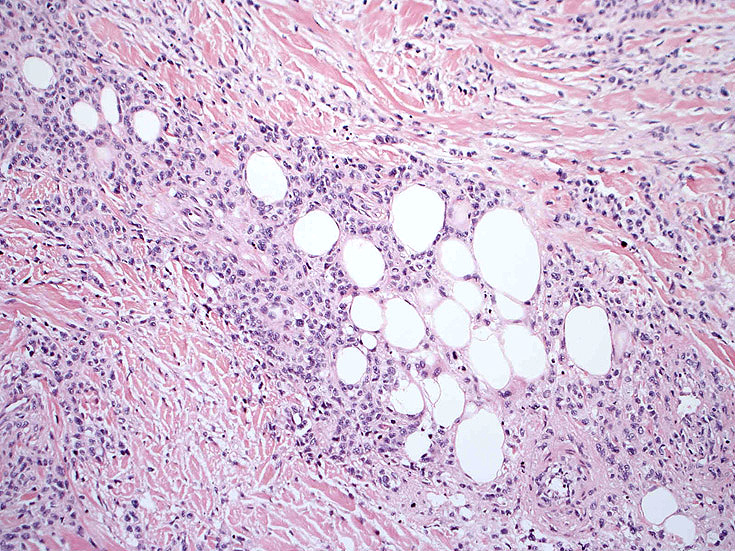

皮膚生検組織。細胞浸潤が表皮, 表皮真皮境界部, 真皮, 皮下組織にびまん性に認められる。血管中心性に結節様の分布があるように見える。

皮膚に異型細胞の浸潤がみられる。異型細胞は表皮内に浸潤するほか、表皮真皮境界部, 真皮, 皮下脂肪組織にもびまん, 結節様の浸潤所見を示す。血管周囲に浸潤、集蔟する所見も多く見られる。 増殖浸潤細胞の核には類円形や腎臓形, またはへこみ, 切れ込み, 溝などを有する多型な核が認められる。クロマチンは粗でvesicularな核が多い。核小体の明らかな核もある。好エオジン性の核内封入体様構造も少数に見られた。mitosisは容易に認められる。hyperchromaticな多型核, bizzarreな細胞が高頻度に認められ異型度は高いと考えられる。細胞質は境界不明瞭, 淡明または泡沫様の 好エオジン性胞体である。